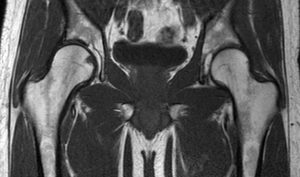

מאת: עופר בן חורין. MRI פרקי ירכיים היא בדיקה יעילה ביותר להדגמת מפרקי הירכיים וסביבתם. ניתן לבצע אותה על מנת לאתר קרעים במפרק, שינויים ניוונים, חבלות למיניהם, זיהומים, גידולים וכל תלונה אחרת המתארת כאב או נפיחות…